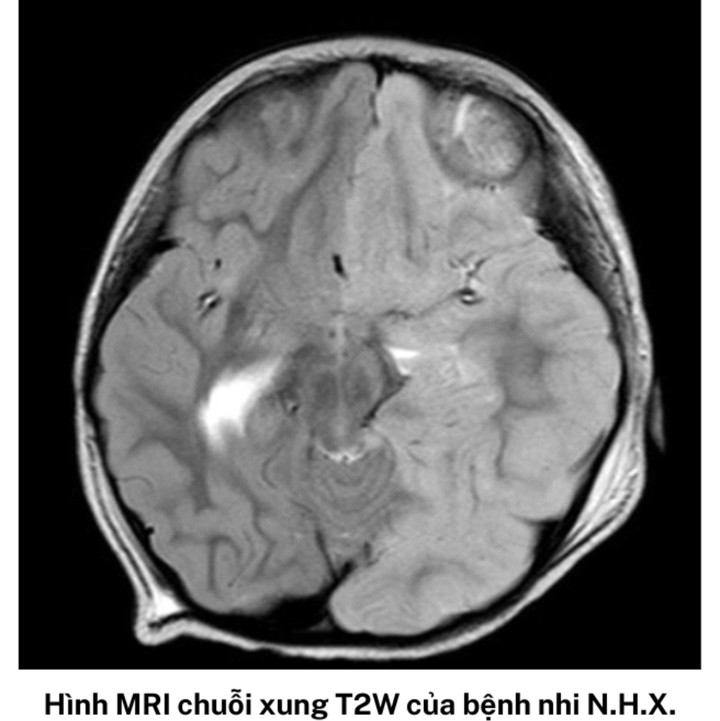

Bệnh nhi N. được đặt nội khí quản, chuyển khoa Hồi sức tích cực Nhiễm. Kết quả MRI sọ não cho thấy bé có tổn thương hạn chế khuếch tán lan tỏa ở bán cầu não trái trong khi vỏ não phải bình thường.

Trường hợp thứ 2 là bé gái N.H.X., sinh năm 2020 (ngụ TP.HCM) nhập viện cuối tháng 5.

BS.CKII Đỗ Châu Việt, Trưởng Khoa Hồi sức tích cực Nhiễm Bệnh viện Nhi Đồng 2 cho biết, kết quả MRI sọ não của bé X. cũng cho thấy có tổn thương kèm phù não gần như toàn bộ nửa bán cầu trái, đẩy lệch đường giữa sang phải, bán cầu não phải bị ép xẹp.